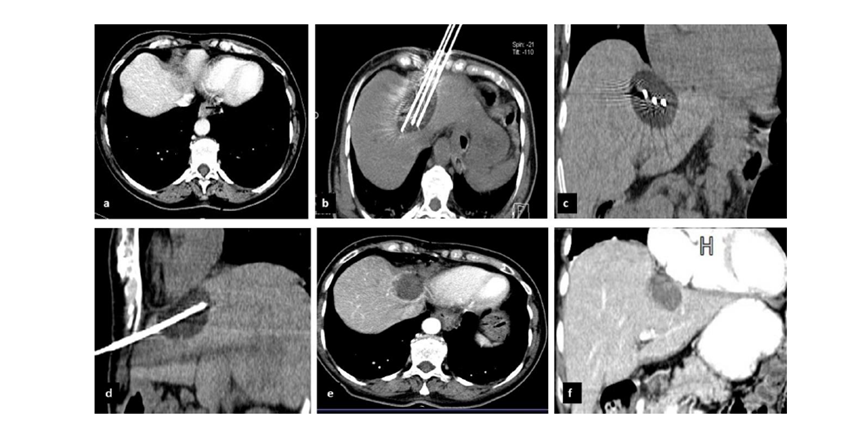

CT引导的冷冻消融

完全消融率为97%(66/68);2名患者均接受了额外的冷冻消融,随后实现完全消融。平均随访期为 12.8 个月(范围:3-27 个月)。所有患者均接受影像复查(CT 或 MRI)。11个病灶(16.2%)检测到局部肿瘤进展,6、12和18个月时的累积局部肿瘤进展率分别为4%、8.2%和20.5%。8例出现远处肝内或肝外病变的患者接受经动脉化疗栓塞、经动脉化疗栓塞加射频消融治疗或全身化疗。

主要和次要并发症发生率分别为3.5%(2/57)和22.8%(13/57)。并发症主要表现为局部皮肤冻伤、中度气胸、发热,仅有少数患者接受治疗,多数患者自行恢复。所有患者能耐受围手术期疼痛,VAS 评分范围在 1-3 分之间(平均 1.65分)。3例患者术后疼痛加重,VAS评分达到4~5分,患者口服止痛药后逐渐缓解。所有患者术后1天血常规、白细胞计数均升高,血小板均有不同程度下降,但变化值均在正常范围内。肝功能1个月后逐渐恢复到正常水平。

(1)经皮冷冻消融治疗包膜下肝细胞癌(HCC)安全有效。(2)经皮冷冻消融治疗包膜下 HCC 的手术过程简单。(3)包膜下 HCC 患者通过冷冻消融治疗可减轻疼痛,并且仅需局部麻醉。冷冻消融是一种微创治疗方法,可用于治疗原发性和转移性肝癌,对于不适合肝切除或肝移植的患者,冷冻消融在临床上得到广泛的应用。本研究的目的是评估冷冻消融对肝细胞癌和肝转移癌患者的有效性。